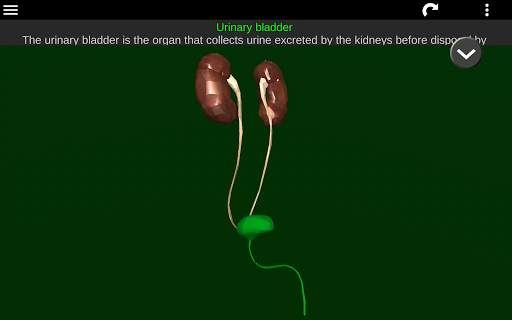

Shows a 3D anatomical model of the main organs of the human body and a description of each one.

* Descriptions of each organ.